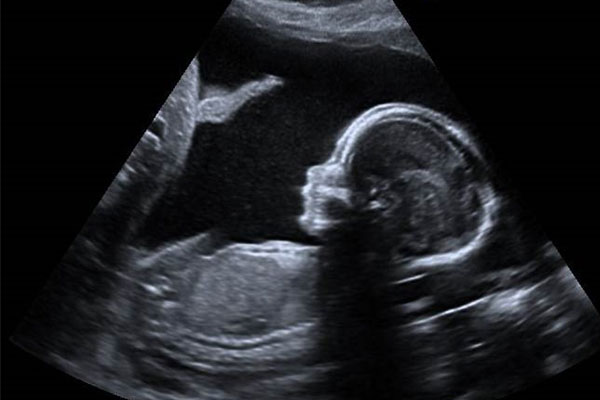

سونوگرافی انومالی اسکن

سونوگرافی آنومالی اسکن (Anomaly Scan) یا سونوگرافی سطح دوم، یکی از مهمترین و حیاتیترین سونوگرافیها در دوران بارداری است که معمولاً بین هفتههای ۱۸ تا ۲۲ بارداری انجام میشود. این سونوگرافی به منظور بررسی دقیق آناتومی جنین و تشخیص ناهنجاریهای ساختاری احتمالی انجام میشود.

هدف اصلی این بررسی، شناسایی اختلالات ساختاری مهم در اندامهای اصلی جنین از جمله مغز، قلب، ستون فقرات، کلیهها و اندامهای حرکتی است. این سونوگرافی یکی از ابزارهای کلیدی در پزشکی مادر و جنین به شمار میآید و میتواند اطلاعات بسیار مهمی را در اختیار پزشک متخصص قرار دهد تا تصمیمگیری مناسبتری در ادامه بارداری انجام شود.